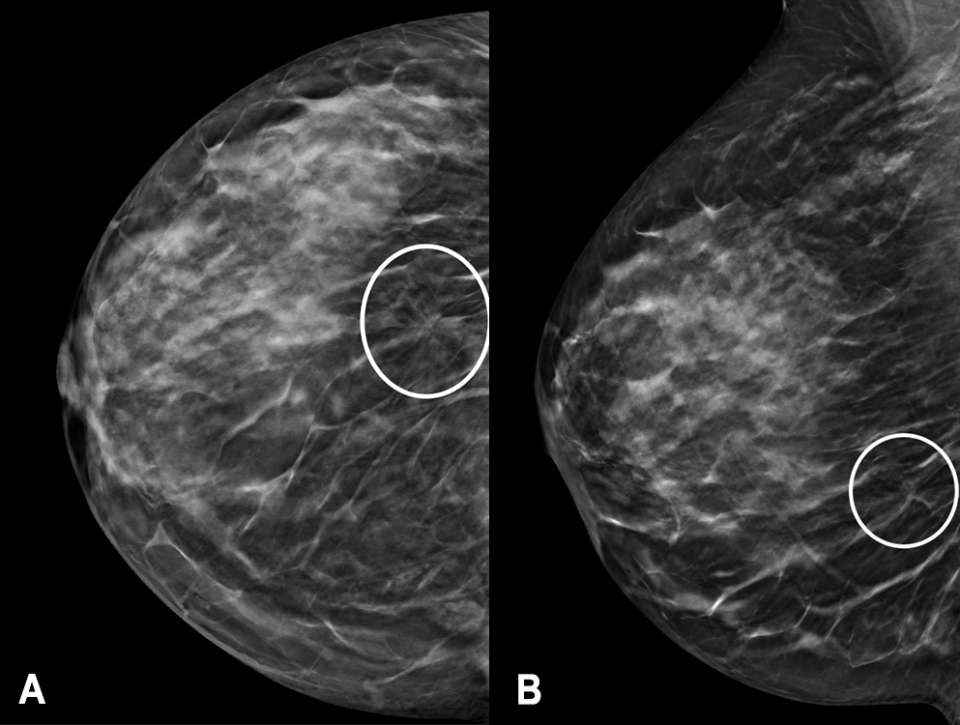

The screening mammogram demonstrated an area of architectural distortion in the lower outer quadrant of the right breast (Figure 1). By the Tyrer-Cuzick version 8 risk calculator, the patient was high-risk, with an approximate 20.3% lifetime risk of developing breast cancer. The mammographic findings were categorized as a BI-RADS 0, and the patient was called back for a diagnostic mammogram with possible diagnostic breast ultrasound.